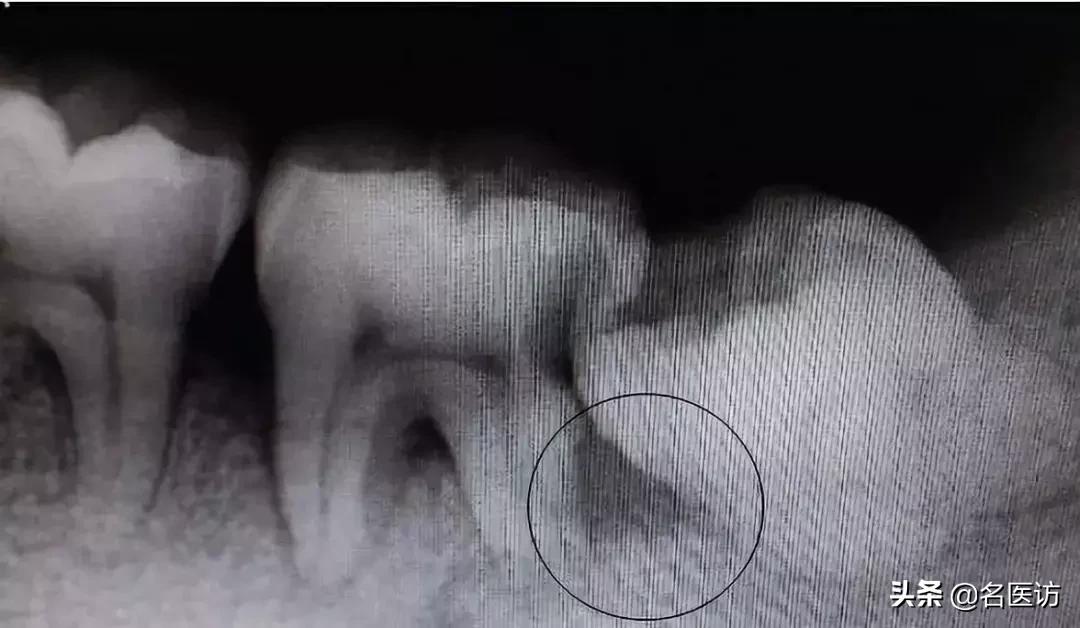

智齿引起下颌骨大面积囊肿